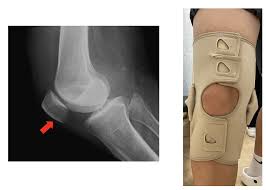

膝蓋骨 骨折膝蓋骨 仕事膝蓋骨 復帰膝蓋骨 膝蓋骨骨折(膝のお皿の骨折)膝蓋骨 -膝蓋骨 埼玉県上尾市、さいたま市北区|すぎやま整骨院膝蓋骨 膝蓋骨骨折「装具を用いた治療例」膝蓋骨 -膝蓋骨 古東整形外科・リウマチ科膝蓋骨 左膝骨折記録膝蓋骨 |膝蓋骨 すてきな毎日膝蓋骨 膝蓋骨骨折日記(1か月目)|ゆきこ膝蓋骨 膝蓋骨骨折、入院から、13日目〜すぐに退院…over膝蓋骨 tha膝蓋骨 rainbow膝蓋骨 |膝蓋骨 美味しいもの、見つけた✨^_^yukari109sakuraのブログ